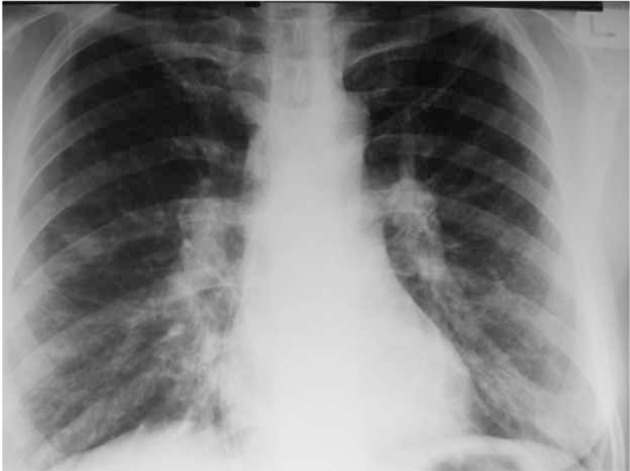

Pre-training data. We use the same dataset as LLaVA-Med (llava-med). Stage 1 includes 600K image-text pairs filtered from PMC-15M, converted into instruction-following data with simple image descriptions. Stage 2 comprises 60K image-text pairs from PMC-15M across five modalities: CXR, CT, MRI, histopathology, and gross pathology. GPT-4 is then employed to generate multi-round Q&A in a tone mimicking visual interpretation, converting these pairs into an instruction-following format.